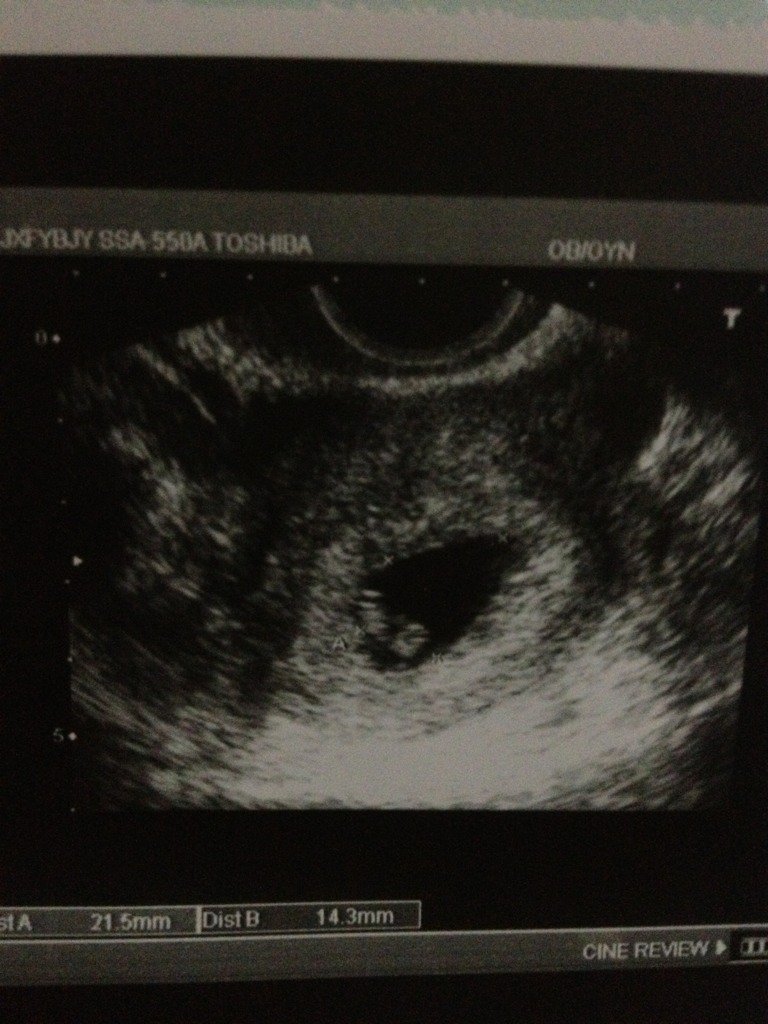

怀孕50天阴超 孕囊21.5*14.3 帮忙看看男宝 女宝

怀孕50天阴超 孕囊21.5*14.3 帮忙看看男宝 女宝😉

你好,根据孕囊大小不能判断是男是女,只能15周以后通过坊尺B超瓦录扬动态观察胎儿性裁院别。